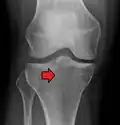

-

Lipohermatrosis (presencia de grasa y sangre provenientes de la médula ósea en el espacio de la articulación después de una fractura interarticular) visto con Rayos-X en una persona con una leve fractura de meseta tibial. -

Lipohermatrosis debida a una fractura de meseta tibial -